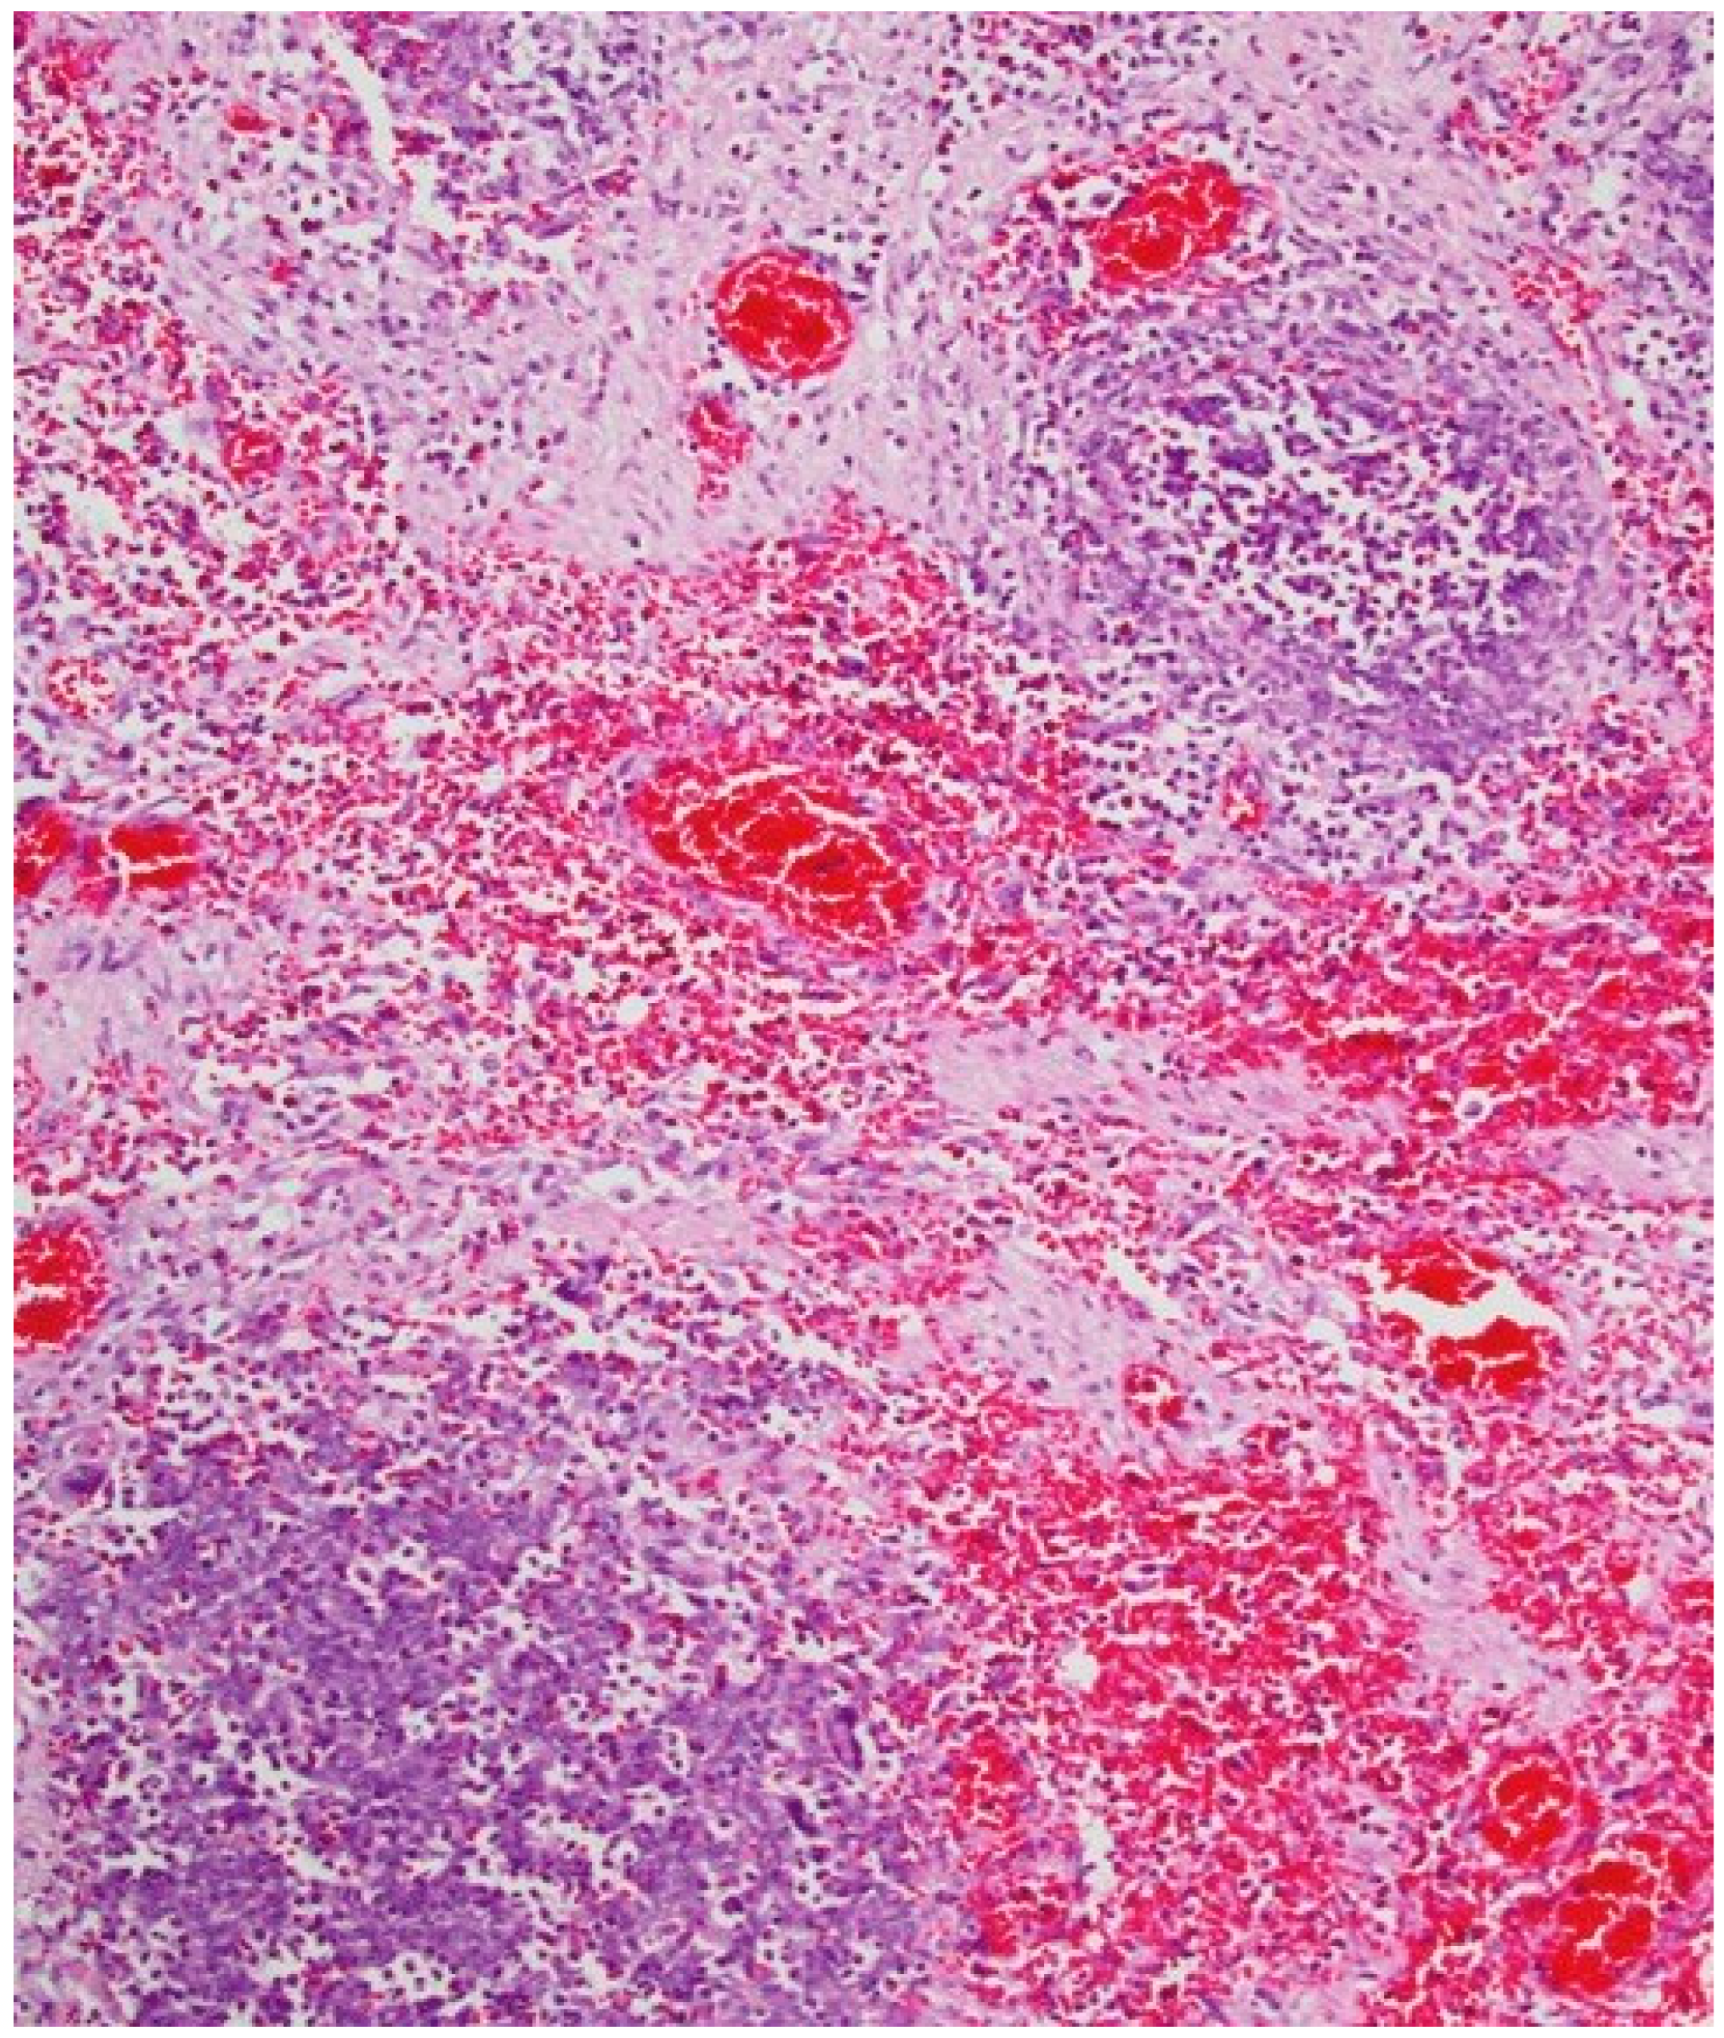

The autopsy evidenced the following: congestion of meningeal vessels; oedema and congestion of both lungs; left ventricular hypertrophy with widespread congestion and sclerosis of both valves and coronaries; inflammation of small intestine and stomach, both presenting a greenish liquid with a very intense smell (see Figure 1); congestion of spleen and kidneys.

Histological exams showed a degenerative myocardiopathy and segmental vascular insufficiency, associated with myocardial micronecrosis foci. Lungs presented diffuse alveolar damage, with chronic interstitial pulmonary disease. Kidney showed necrotic degenerative changes of the tubules and glomeruli with interstitial nephritis (see Figure 2). The presence of the greenish liquid was confirmed in the stomach and in the small intestine, with both presenting mucosal inflammation and gastric necrotic areas (see Figure 3). Finally, there was mild fatty liver disease.

Figure 1. Internal stomach walls with areas of inflammation.